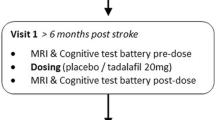

All data are from a cohort of older adults with radiological and clinical evidence of symptomatic SVD (N=54, demographic details in Table 1). These participants were all recruited as part of a double-blinded, placebo-controlled, phase-II clinical trial, Perfusion by Arterial spin labelling following Single dose Tadalafil In Small vessel disease (PASTIS; European Union Clinical Trials Register number 2015-001235-20, registered 13/05/2015) [17]. The trial received ethical approval from the UK National Research Ethics Service (REC reference: 15/LO/0714). Further details are given in the Supplementary file.

Participants attended an initial screening visit (“visit 0”) and completed an eligibility check and gave informed consent. During the screening visit, education level and Montreal Cognitive Assessment (MoCA) scores were recorded (see Table 1). Following consent, participants attended two study visits (visit 1, visit 2) at least 7 days apart as specified in the study protocol [17]. At each study visit, participants underwent systolic/diastolic blood pressure (SBP/DBP) measurement, a cognitive test battery (see Supplementary file) and brain MRI scanning including pCASL. Participants then received either drug or placebo, according to the cross-over design, after which blood pressure, cognitive and MRI measurements were all repeated. All data reported here are from the set of measurements prior to treatment with drug or placebo.

Inclusion criteria were as follows. 1, radiological evidence of SVD, defined as: MRI evidence of lacunar infarct(s) ≤ 1.5 cm maximum diameter and/or confluent deep white matter leukoaraiosis (≥ grade 2 on the Fazekas scale). 2, Clinical evidence of cerebral small vessel disease defined as either: lacunar stroke syndrome with symptoms lasting >24 hours, occurring at least 6 months prior to visit 1; or: transient ischaemic attack lasting < 24 hours with limb weakness, hemi-sensory loss or dysarthria at least 6 months previously and with MR DWI performed acutely showing lacunar infarction. If MRI was not performed within 10 days of TIA, a lacunar infarction in an anatomically appropriate position as demonstrated on a subsequent MRI was also deemed eligible. 3, Age ≥ 50 years. 4, imaging of the carotid arteries with Doppler ultrasound, CT angiography or MR angiography in the previous 12 months, demonstrating < 70% stenosis in both internal carotid arteries or < 50% stenosis in both internal carotids if measured in previous 12-60 months.

CBF maps were generated using pCASL in a cohort of older adults (age 66.9 (8.7) range: 52-87 years, N=54) all of whom had symptomatic SVD (Table 1, example in Figure 2). All participants had survived a lacunar stroke, and visit 1 occurred at least six months post-stroke. All participants completed visit 1 and visit 2 at least 7 days apart (mean (SD): 20 (19) days, range 7-117 days). Only four participants completed visit 2 more than 30 days after visit 1 (range 54-117 days). If these four participants were excluded, none of the parameters reported below changed significantly (P values in the range: 0.733 to 0.994; not shown).